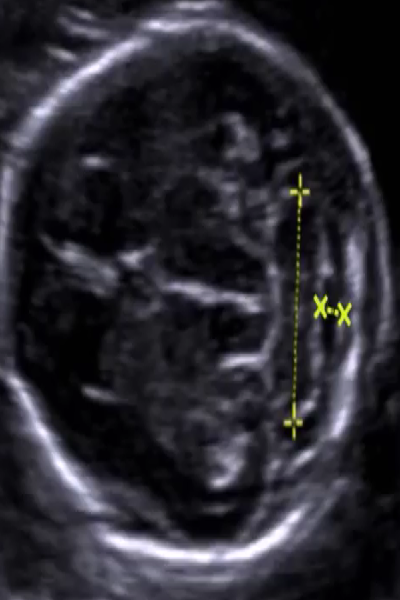

小脑横径

2021-10-22